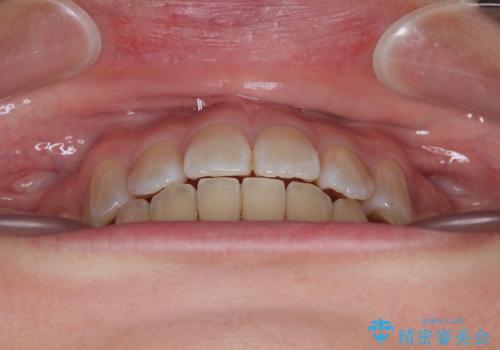

- 上下顎前歯部の非接触(開咬)と下顎のデコボコを主訴に来院された患者様です。

右側上下と左上の小臼歯が一本ずつ少なく、さらに骨格的な左右差もあり上下の真ん中の位置がずれています。

下顎のデコボコの解消と、真ん中の位置を改善するために左下の小臼歯を抜歯することとしました。

また、開咬を改善するため臼歯部にアンカースクリューを用いて圧下する力をかけていきました。

舌を突出する癖があり、それにより開咬が悪化したり、後戻りの原因になるため、舌のトレーニング(MFT)も行いました。

舌のトレーニングは継続して行ってもらっているため、開咬や抜歯したスペースの後戻りはなく、経過は良好です。